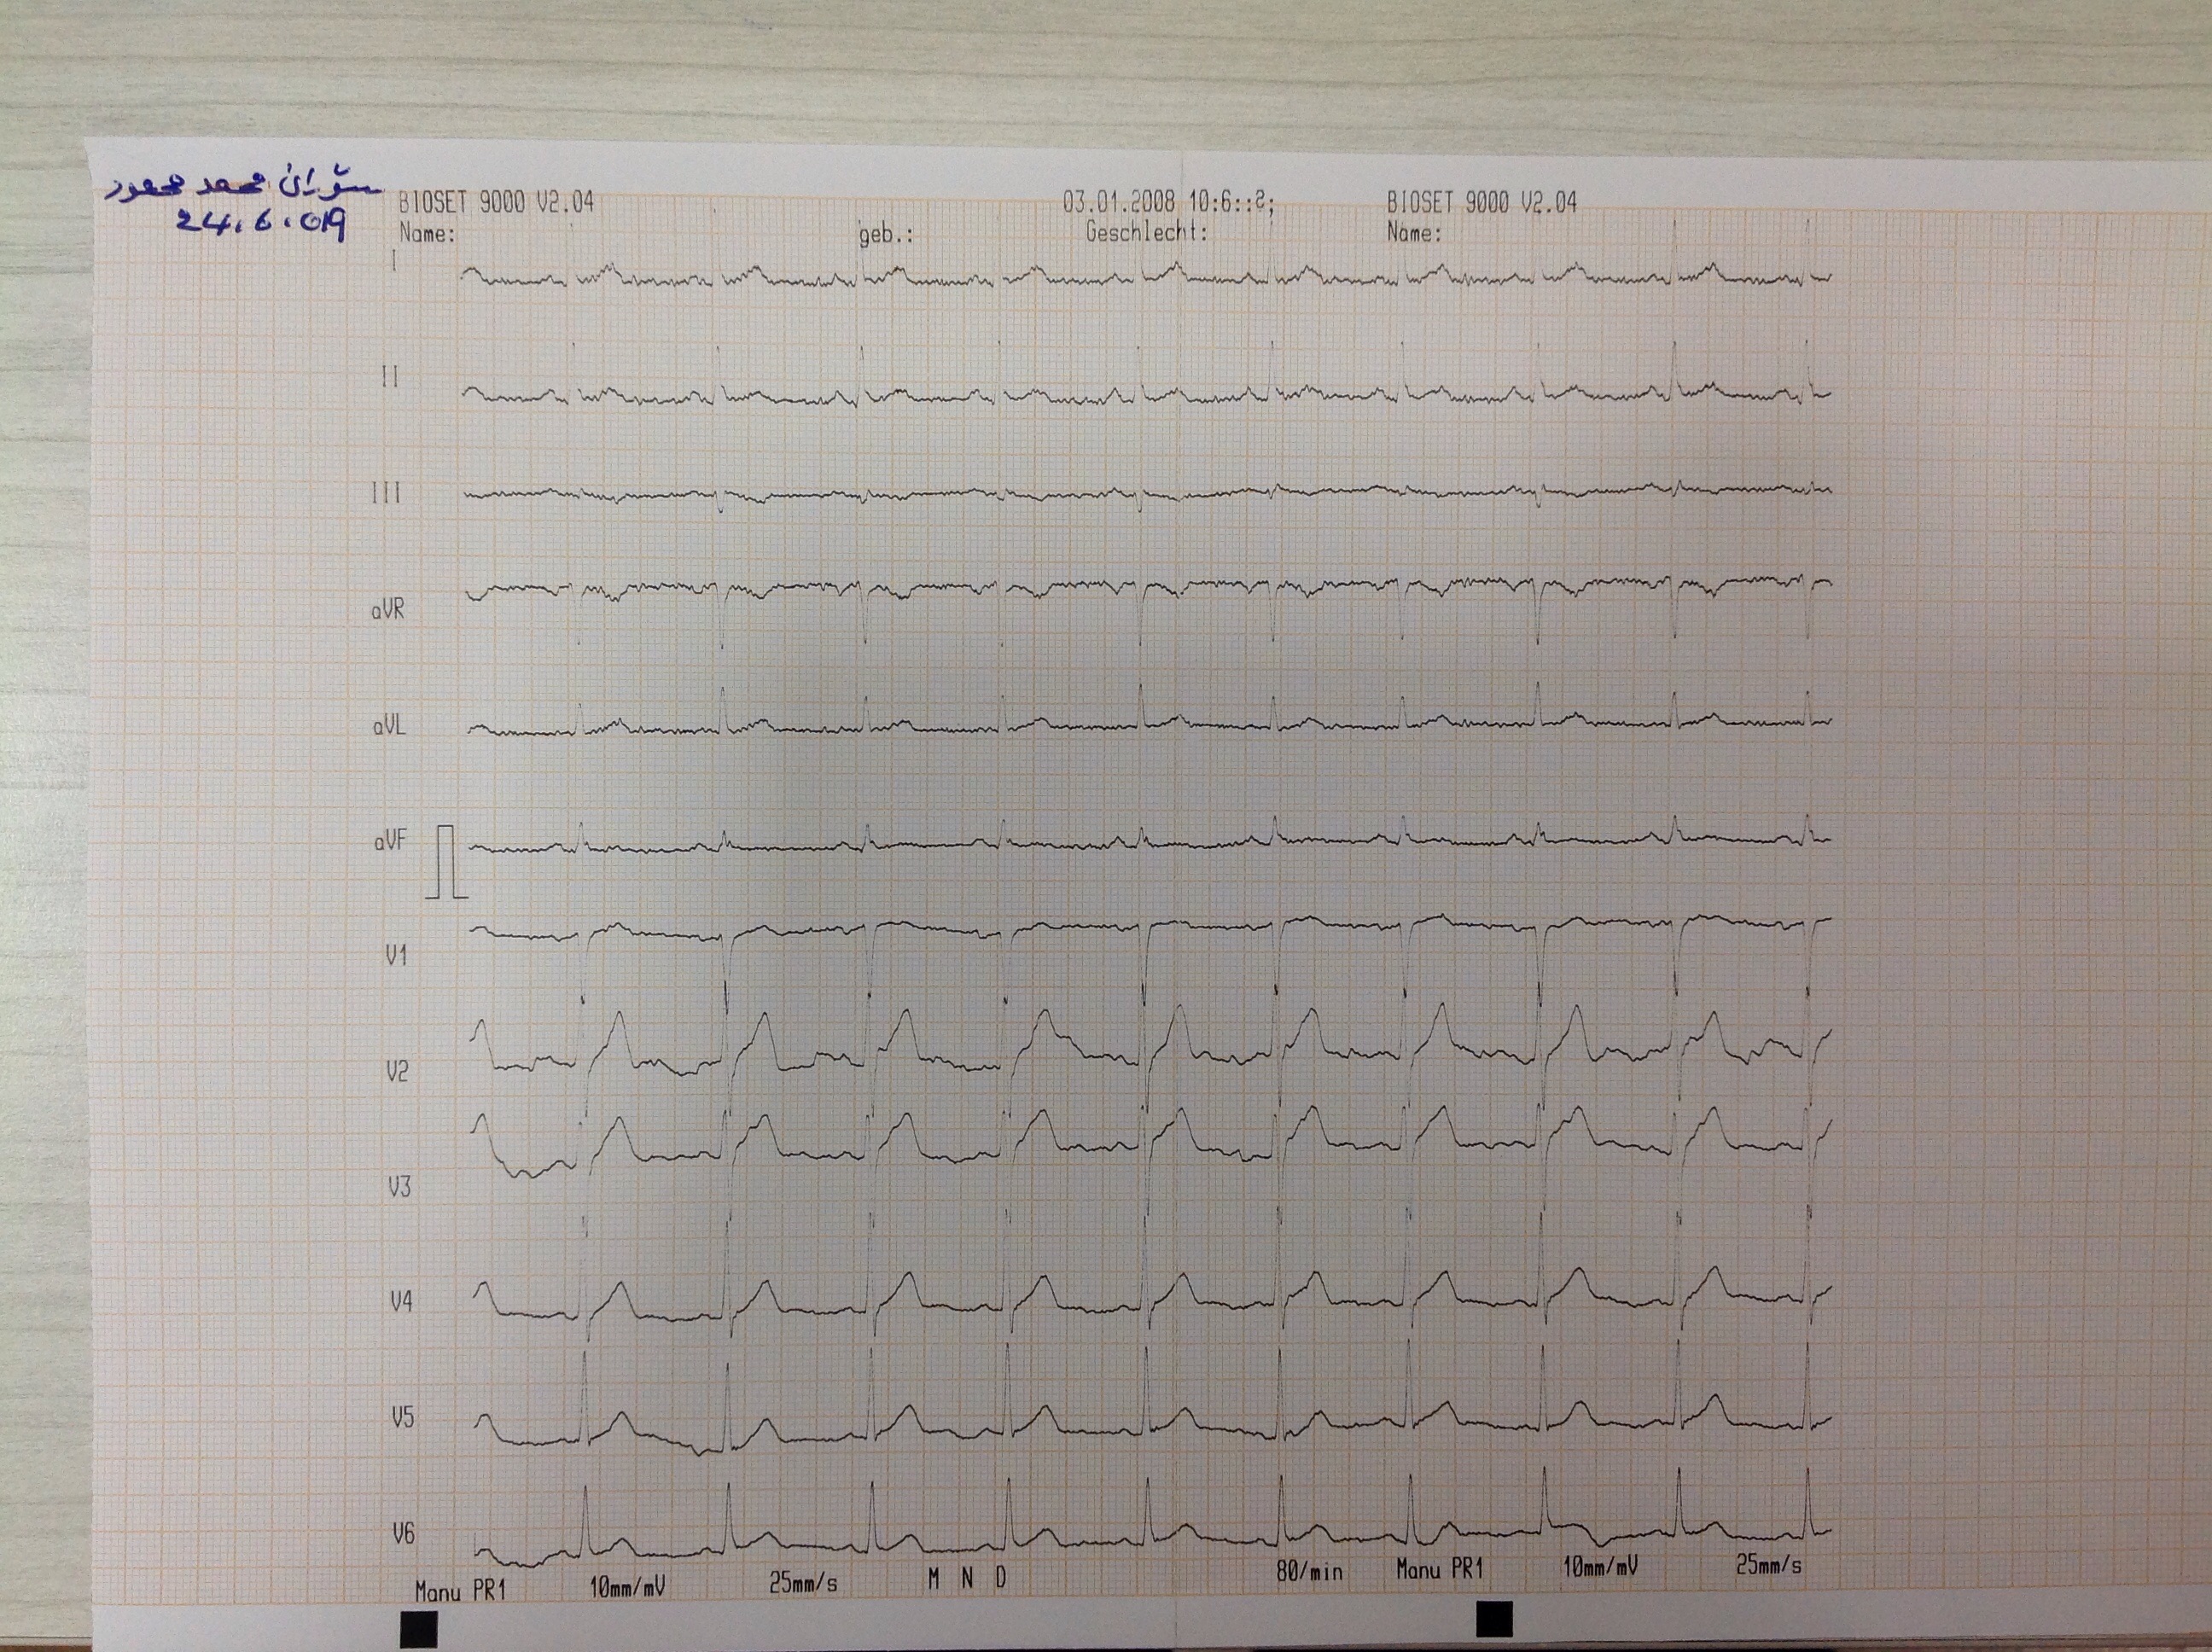

BP : 135/80     PR : 94     RR :     SPO2 : 97     CC : chest tightness with dyspnea for aweek

ID : 280      soran mhammad mahmud           1983             Male      W : 96.7 kg     H : 165 cm         Alcohol        Smoking     HPI :

12019-06-23 17:31:49